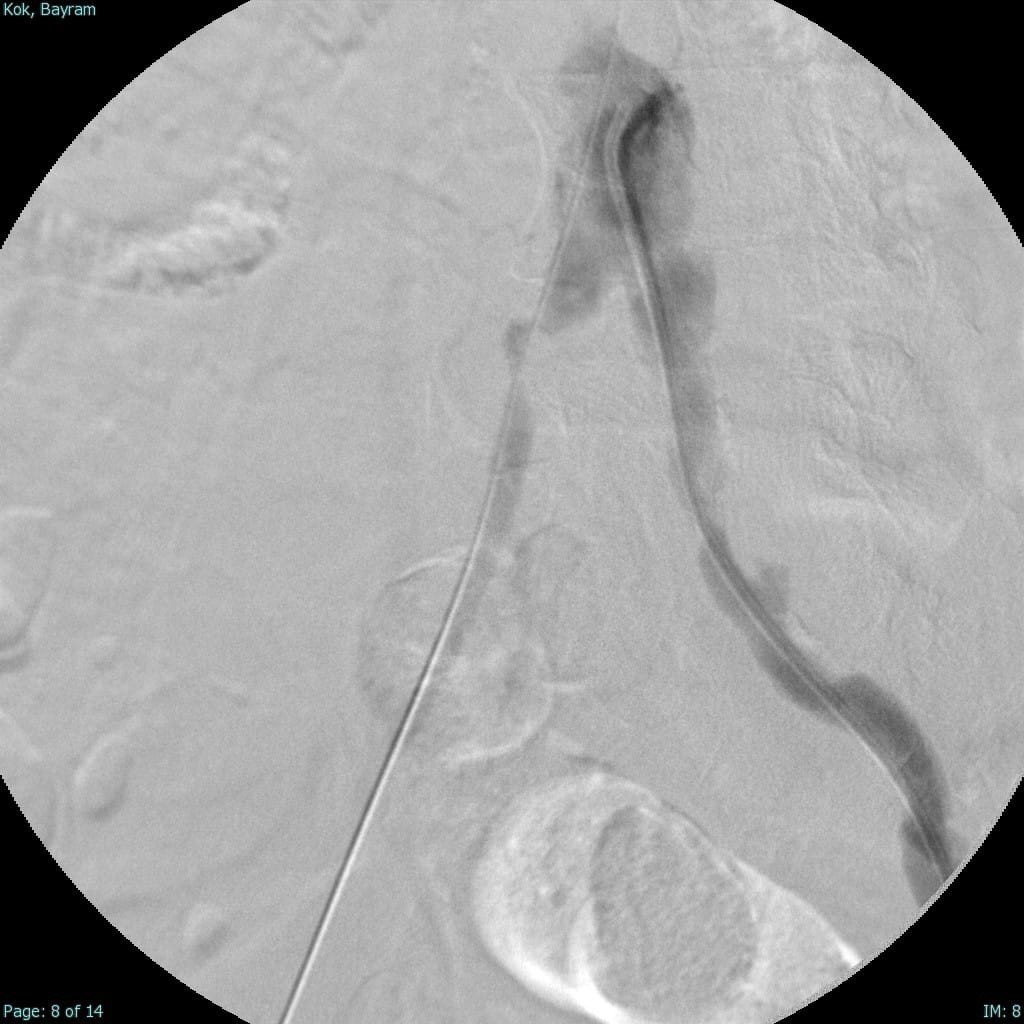

Türkiye'nin ilk yerli stent grefti Bezmiâlem Vakıf Üniversitesi Tıp Fakültesi'nde Prof. Dr. Cengiz Köksal ve Doç. Dr. Emre Selçuk'un öncülüğünde Artven koordinasyonuyla bir hastaya başarıyla uygulandı. Doç. Dr. Emre Selçuk, bu büyük adımı şöyle değerlendirdi:

"Stent-greft teknolojisi, damar tedavilerinde kritik bir rol oynuyor. Damar balonlaşması veya yaralanma riski olan hastalarda bu teknolojinin önemi daha da artıyor. Artık bu teknolojiyi Türkiye'de üretiyor olmamız, operasyon başarımızı artırmanın yanı sıra, hasta güvenliğini de üst seviyelere taşıyacaktır. Türkiye'nin tıbbi alandaki bu başarısında yer almaktan büyük gurur duyuyoruz. Atlas Stent Greft, Türk mühendisliğinin ve Türk doktorlarının inovasyonunun ne kadar ileri seviyede olduğunun bir göstergesidir."